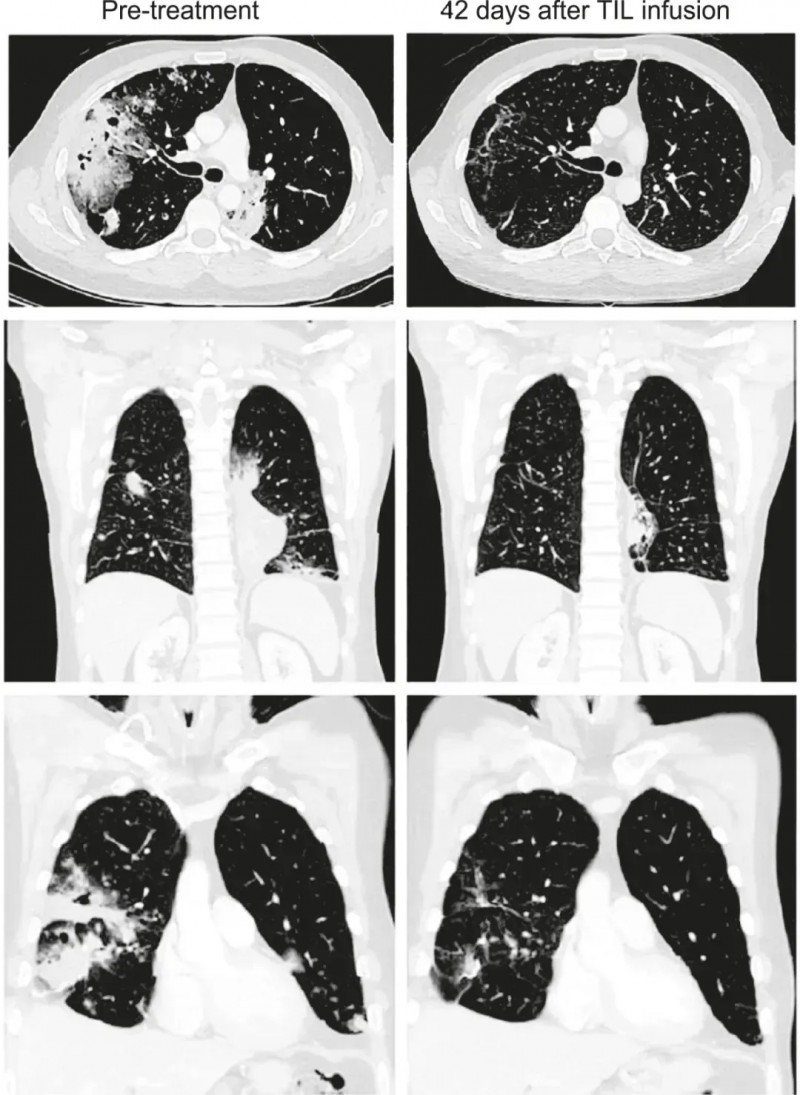

该患者是一位41岁IV期粘液性肺腺癌男性,携带KRAS G12D突变,肿瘤突变负荷(TMB)仅为3.3mut/Mb,且PD-L1表达为0%,属于传统免疫治疗获益极低的人群。然而在接受Lifileucel治疗12周后,依据RECISTv1.1标准评估,其部分缓解(PR)率竟高达81%(详见下图)。这一突破性成果,充分彰显了Lifileucel疗法超越传统免疫治疗局限的强大实力。

▼该患者接受TIL治疗前、治疗后6周的CT扫描对比

▲图源“Cancer Discov”,版权归原作者所有,如无意中侵犯了知识产权,请联系我们删除